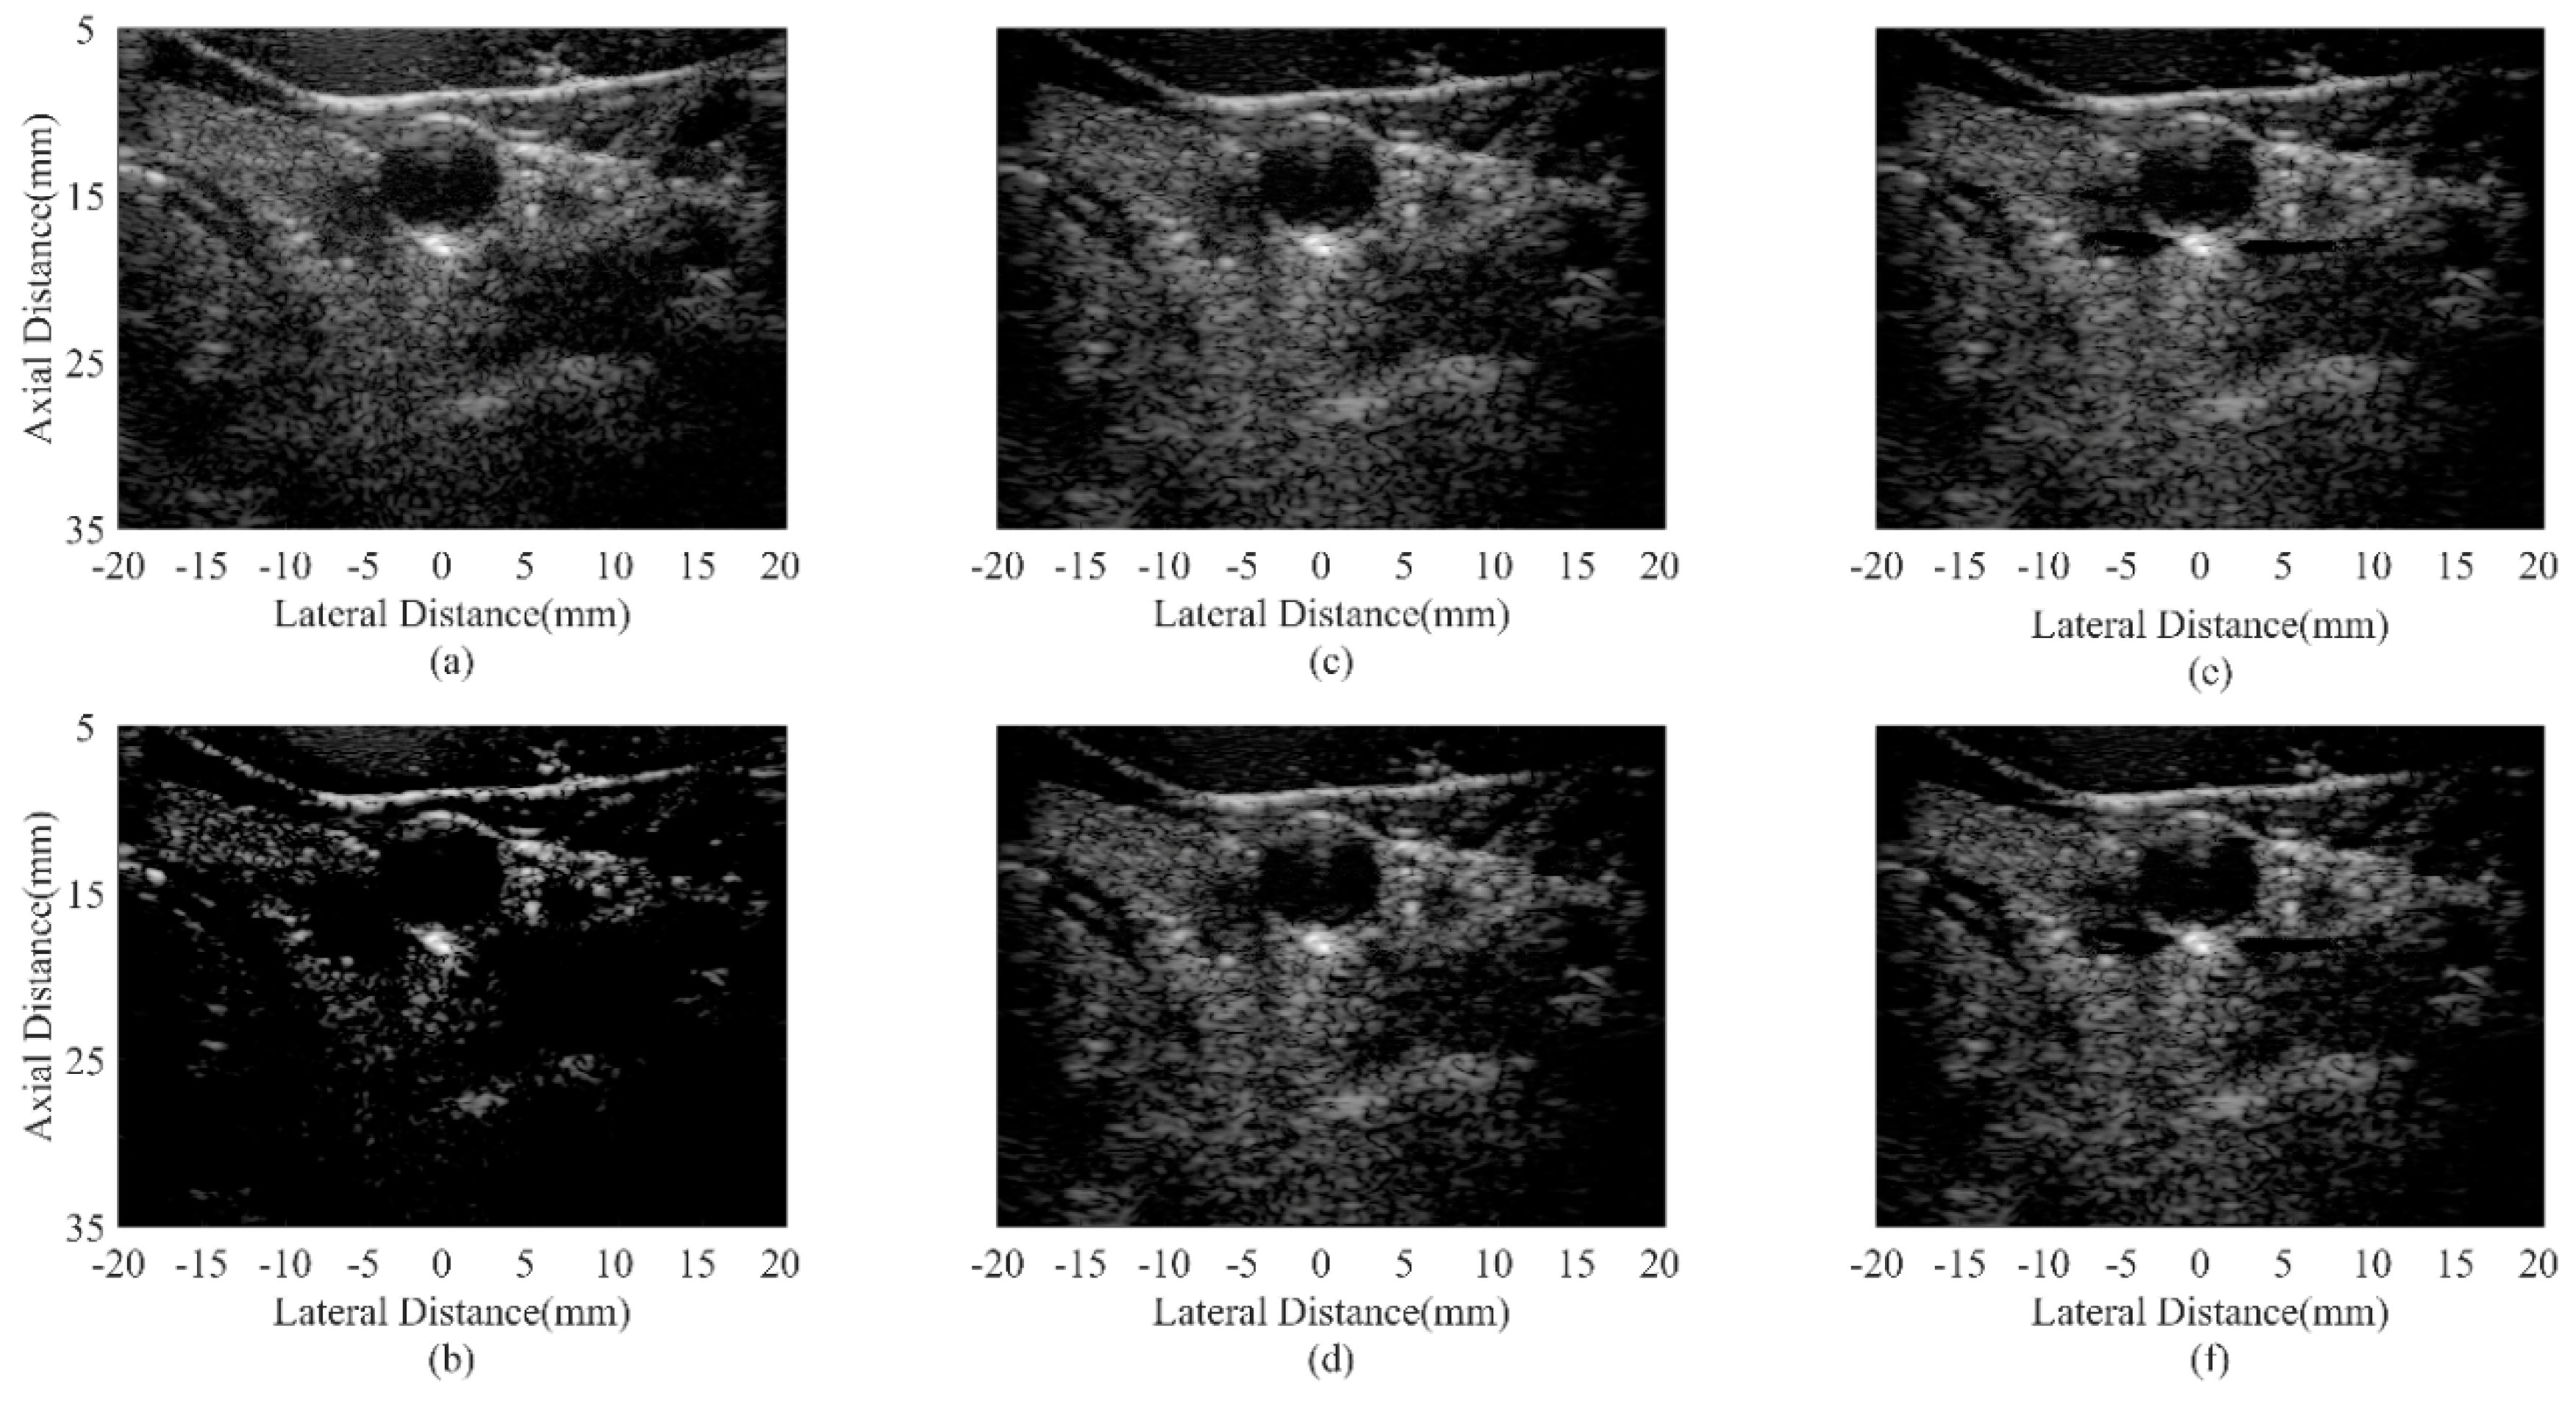

| Beamformer | CR (dB) | CNR |

|---|---|---|

| DAS | 30.32 | 1.76 |

| CF JTR-MV JTR-MV GCF JTR-ESBMV JTR-ESBMV GCF | 76.77 29.87 33.27 50.97 64.01 | 1.13 1.82 1.74 1.86 1.78 |